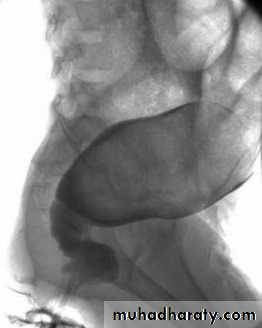

Barium enema :

(Narrow segment distally, transitional zone, dilated segment proximally).

Recto-sigmoid ratio less than 1 (transvers diameter of rectum / transverse diameter of sigmoid).

Retention of contrast material in the colon more than 24hr post filming.

Neonate with HD may have false –ve result.